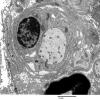

PERIPHERAL NEUROPATHY

7B CIDP (13)